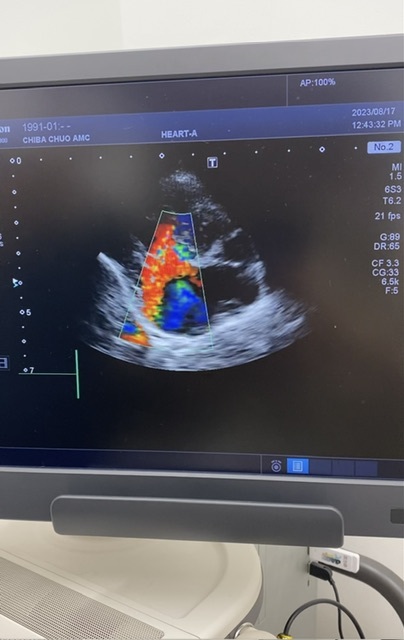

・心エコー

相変わらずの血液検査の逆流

前回と大きく変化はなし